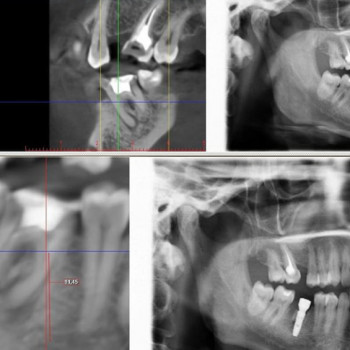

Панорамный снимок зубов в Херсоне

- Компьютерная томография зубов

- Панорамный снимок зубов

- Рентген зубов